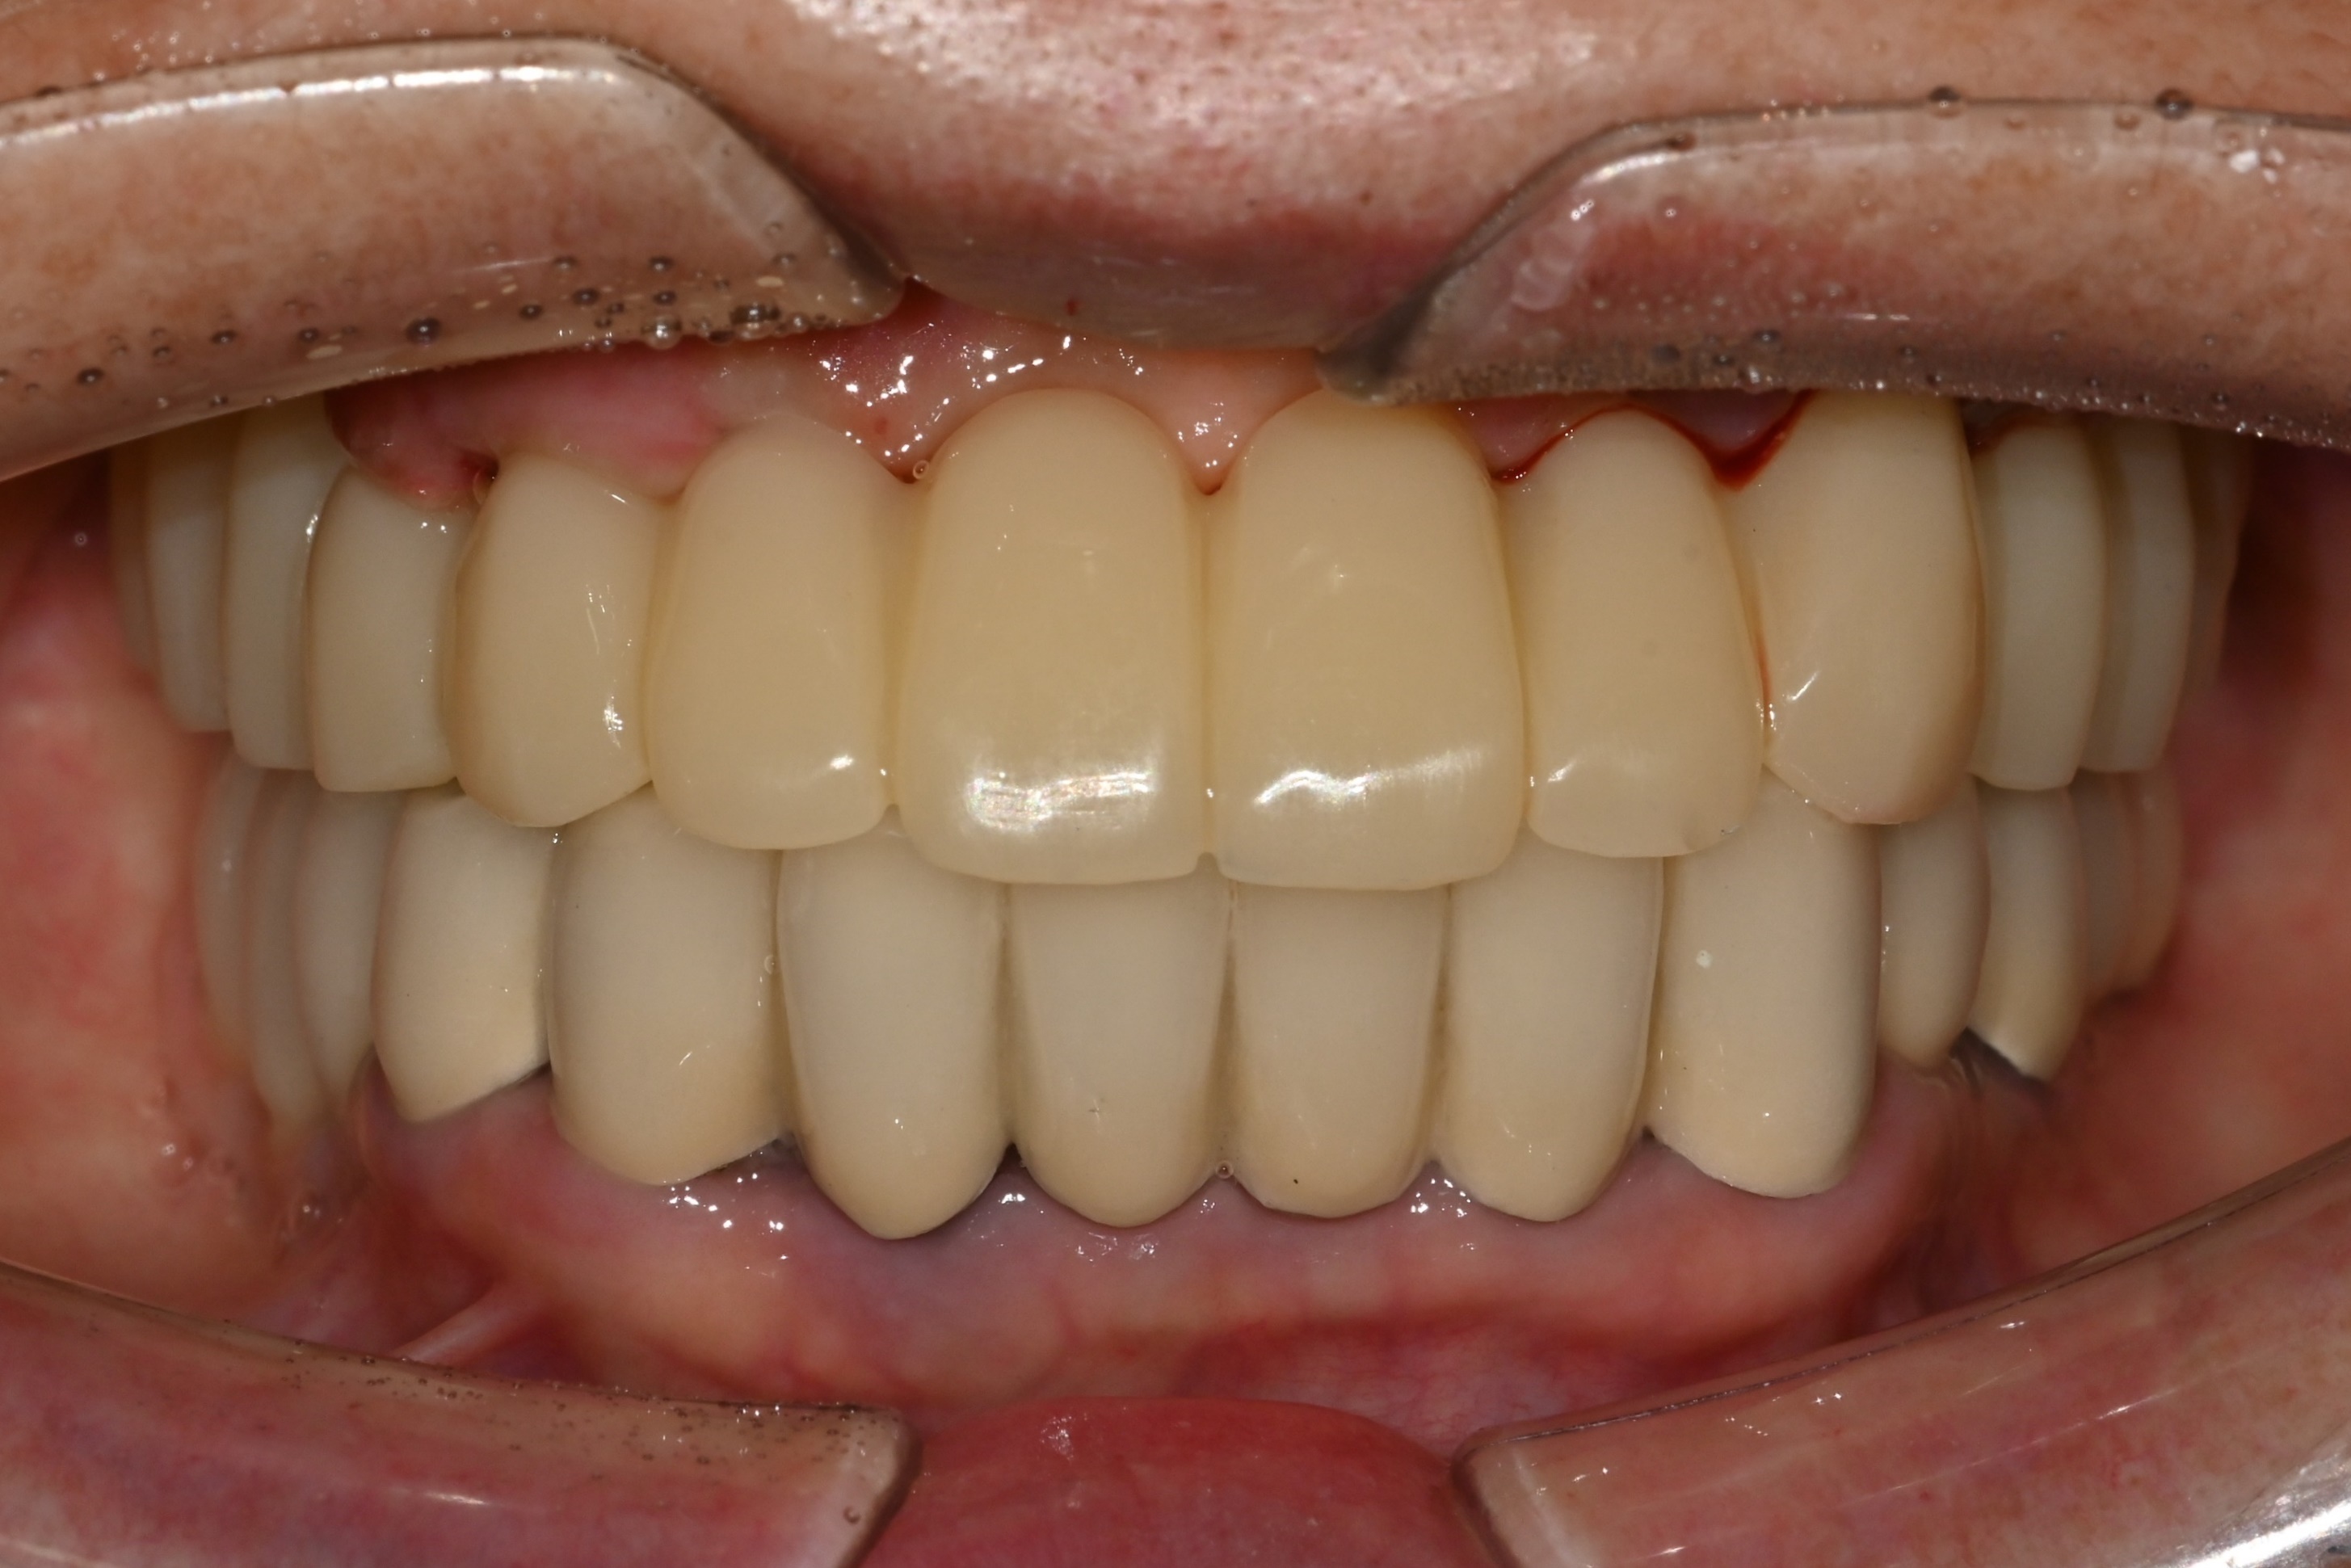

식립하고나서 바로 다음날

고정식 임시보철(임시치아)를

장착해드렸습니다.

잇몸이 안정되고 뼈가 자리 잡는 동안

발음·심미·식사 기능을 유지하는

중요한 역할을 합니다.

임시보철이라도

최종보철에 가까운 완성도

제작하기 때문에

일상생활에

큰 불편 없이 지내실 수 있습니다.